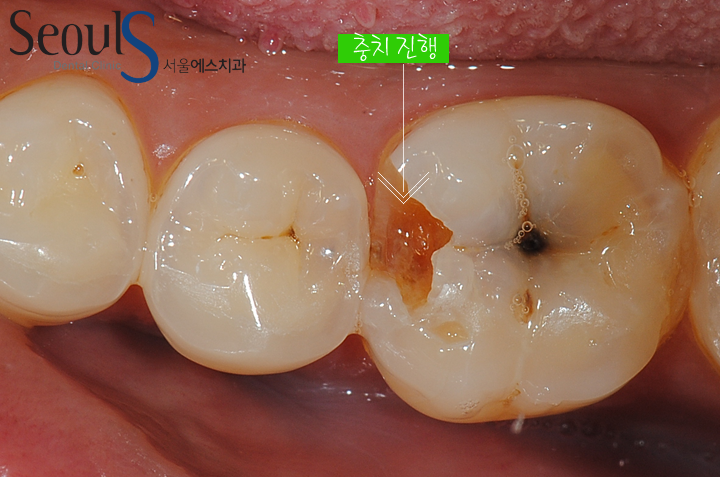

충치가 진행되고 있습니다

충치를 제거하던 도중 치아 속에서 맑은 피가나고 있습니다

치아의 상아질을 삭제하는 과정에서 치수 조직이 노출 되었고 치수에서 피가나는 모습입니다

예전에는 충치치료시 치수가 노출 되면 바로 신경치료를 진행했지만

저희 서울에스치과에서는 신경치료 대신 MTA 신경보호 치료를 진행합니다

단, MTA 치료는 치수 조직에 염증이 없거나 염증 초기일때만 치료가 가능합니다

만약 염증이 오랫동안 진행되서 맑은 피가 아닌 탁한 피가 나면

MTA 신경보호 치료는 불가능합니다